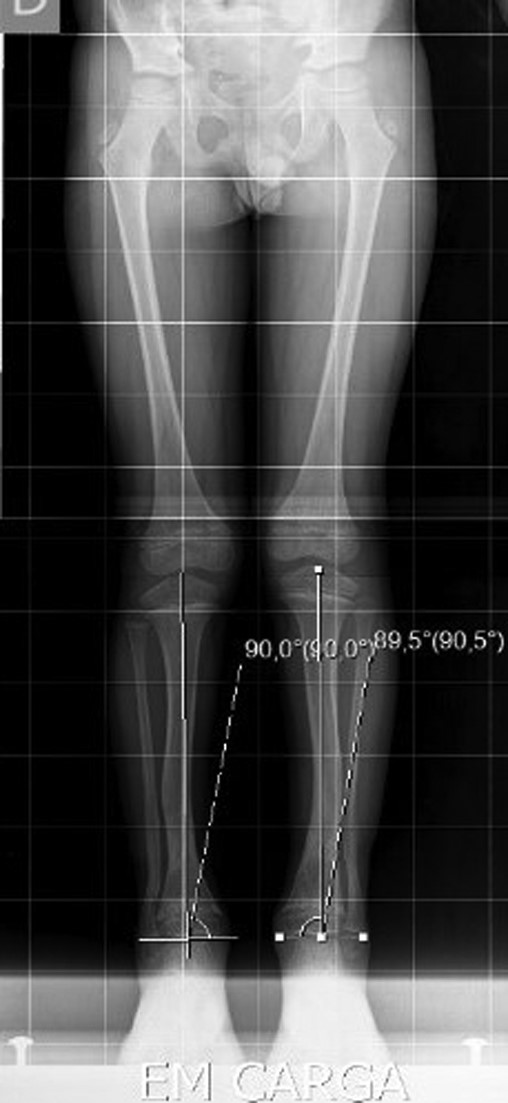

The X-ray showed a bowing of distal tibia, bilaterally, producing a varus deformity of 53 degrees (Fig. 2).

After 1-year of follow-up, the patient presented with normal gait and no callosity (Figs 5 and 6). The long-leg standing X-rays demonstrated a correct alignment of the tibia in the anatomical and mechanical axis (Fig. 7).